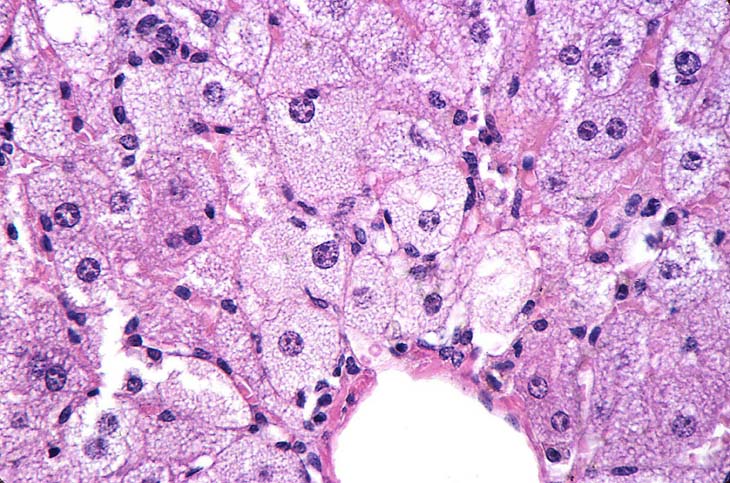

This represents an example of microvesicular fatty change. Multiple small vacuoles present within the hepatocytes give the cytoplasm a foamy appearance.

This example of fatty change represents a combination of microvesicular and macrovesicular fatty change with a distinct lobular pattern. The macrovesicular fat is localized at the periphery and probably represents condensation of microvesicular vacuoles.